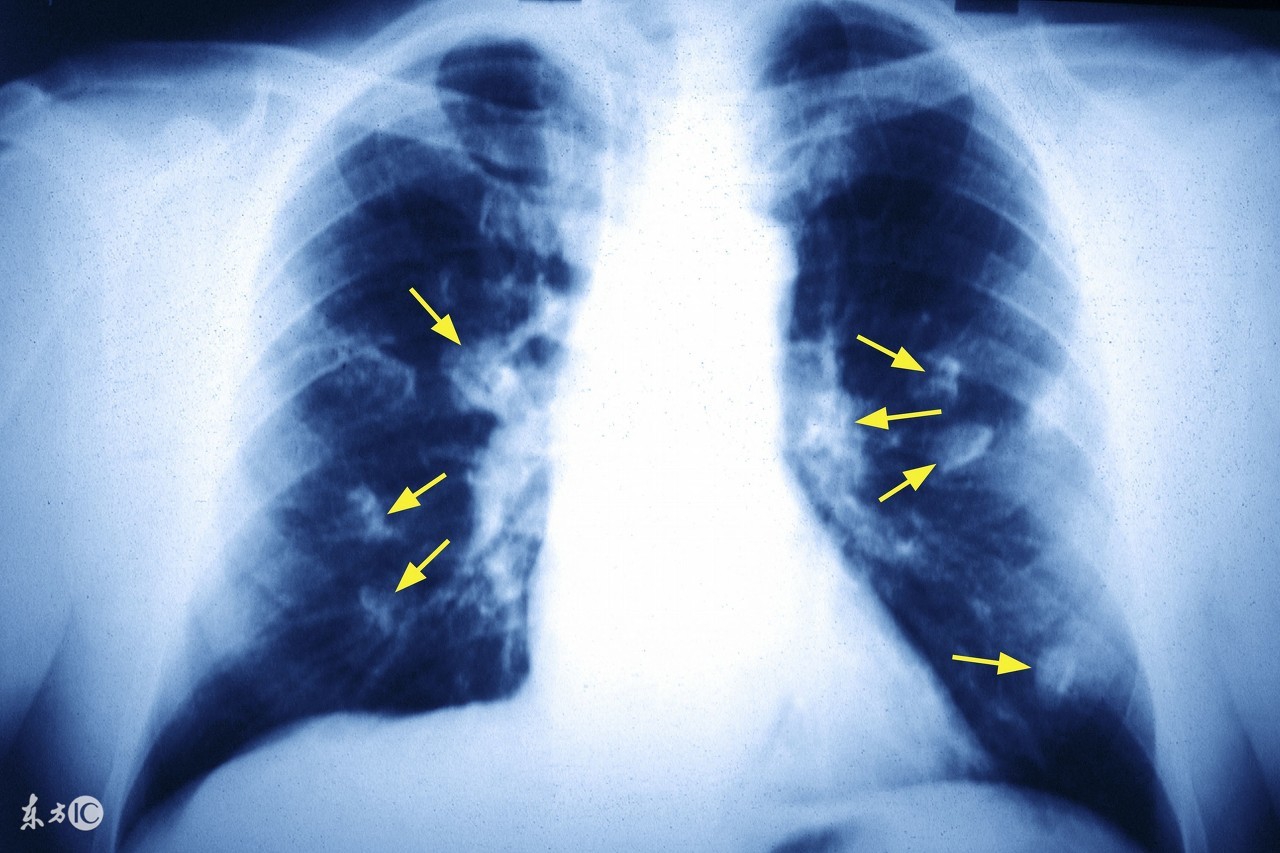

近些年来肺癌的发病率是越来越高了,成为威胁人类健康的重要“杀手”之一,一说到肺癌大家就会想到死亡,但是近些年来随着医学技术水平的不断提高,肺癌的治疗得到了很大的提高,因此大家也不必太担心了。大多数已发生胸内区域性播散的肺癌患者均有胸痛之症状,其次是声嘶。最后还会导致面、颈部水肿。最终,发生区域性扩散的肺癌患者几乎都有不同程度的气促。那么肺癌治疗不及时会导致哪些并发症呢?下面我们一起来了解一下吧。